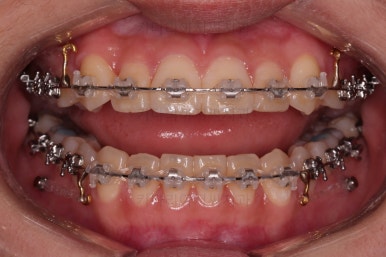

이번에 사용한 장치는 엠파워 클리어라고 하는 자가결찰 세라믹 장치인데요.

철사를 잡아주는 뚜껑이 브라켓에 달려있어 스스로(자가) 철사를 잡을 수 있는(결찰) 장치라는 뜻인데요. 대표적으로는 클리피씨라고 하는 장치가 있습니다. 클리피는 일본장치, 엠파워는 미국장치라는 차이점만 있고 큰 틀에선느 동일한 장치라고 볼 수 있습니다.

이제부터는 미니스크류를 이용해서 치열을 뒤로 잡아당겨 주면서 뻗침이나 벌어져 보이는 형태를 개선해 줍니다.

점점 느낌이 좋아지는 걸 볼 수 있죠?